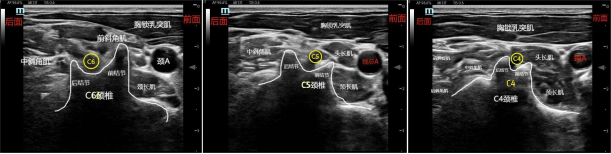

3、第6颈椎:一般C6的前结节非常发达,后结节较短,这一特点,超声显像呈一手指笔画的“手枪”图形。同时前结节的前方非常靠近颈总动脉,因此颈总动脉的声像图像也可以作为定位C6的补充依据。临床上由于C6前结节发达,又靠近颈总动脉,常做为压迫颈总动脉止血的位置。

1、C7、C6、C5、C4颈椎定位法:C7颈椎:探头先放在锁骨上方,利用C7颈椎横突的前结节不明显的特点,上下滑动寻找到C7颈椎的横突,C7的后结节超声图像为一粗大“斜坡”或“椅背样”的骨骼声影。然后上下滑动,当往上滑动时,找C6颈椎,C6颈椎的前结节长,后结节短,呈手指笔画的“手枪”声像图形。再往上滑动探头找C5颈椎,C5颈椎的前结节和后结节一般长短相当,两者的夹角也较大,呈“大V字母”型的声像图像。探头继续往上平移,C4颈椎的前后结节较短,两者的夹角也较小,称为“小V”。